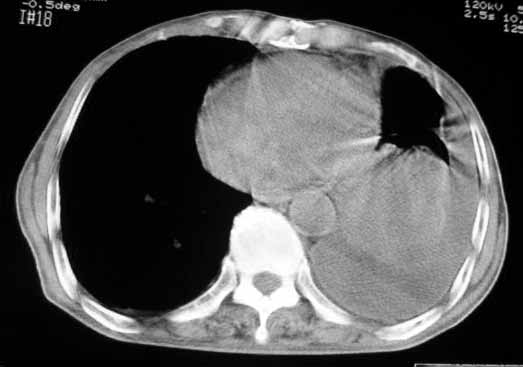

以下是引用luochengyi在2007-5-24 14:33:00的发言:[br]考虑左下肺癌。左侧胸腔积液。

以下是引用adams在2007-5-24 17:12:00的发言:[br]支持“考虑左下肺癌,左侧胸腔积液,建议胸水检查”。[br] [br]

以下是引用fumaogui在2007-5-24 16:20:00的发言:[br]左侧胸腔积液.[br]左下叶不张考虑中心型肺癌[br]建议纤支镜检查.